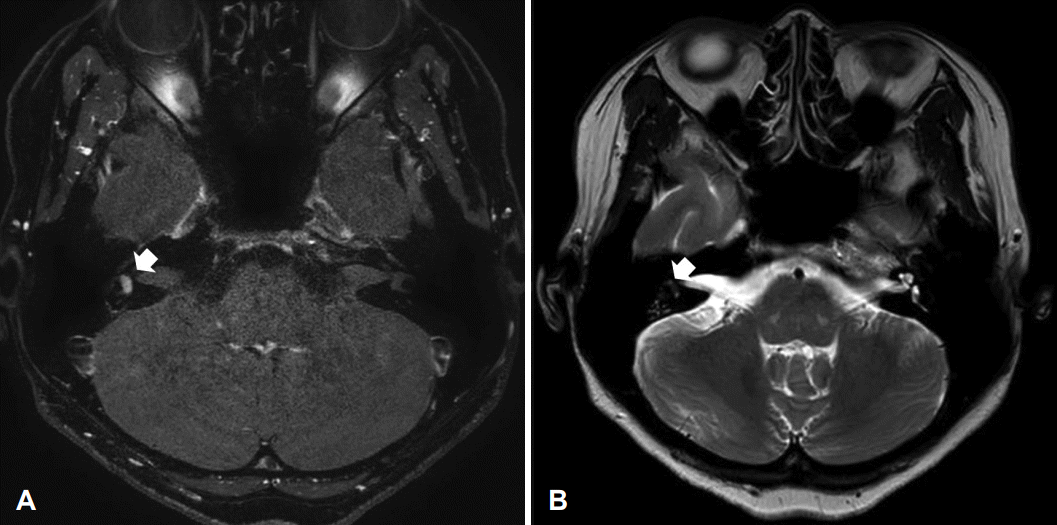

Fig. 2.

MR images. A: T1-weighted, Gd-enhanced axial image shows 0.4 cm sized focal enhancing mass in left vestibule (arrow). B: T2-weighted axial image shows a space-occupying lesion in the left vestibule (arrow).

70세 여자 환자가 1년 전부터 좌측 귀의 지속적인 이명 증상 및 어지럼증 증상이 발생하였으며 보행 시 보행장애 증상 호소하며 외래 내원하였다. 내원 당시 시행한 이학적 검사상 양측 고막 정상 소견이었으며, 청력검사에서 순음평균역치는 우측 25 dB, 좌측 72.5 dB을 보였다. 최대 어음 명료도는 우측 100%, 좌측 60%, 고막 임피던스 검사는 양측 정상 소견이었다. 온도안진 검사에서 좌측 반고리관은 우측에 비해 25% 정도의 마비 소견을 보였으며, 자발안진 및 체위 변화에 따른 안진은 보이지 않았다. 비디오 두부충동검사에서 양측 모두에서 시선재고정 단속운동(catch up saccade)은 관찰되지 않았으며, 전정유발 근전위 검사에서 좌측이 우측에 비해 63% 정도 진폭이 감소된 소견이 관찰되었다(Fig. 1). 측두골 자기공명영상검사(temporal bone MRI)를 시행하였는데 좌측 전정 내에 T1 강조영상에서 고신호강도로 관찰되며 T2 강조영상에서는 충만 결손 소견이 관찰되는 0.4 cm 정도 크기의 미로내 종괴가 발견되었다(Fig. 2).

미로내 신경초종에 대한 진단을 위해서는 조영제를 이용한 측두골 자기공명영상이 필요하다[5]. 종양은 일반적으로 T1 강조영상에서는 조영 증강을 보이며 T2 강조영상에서는 음영 결손을 보이는 양상을 보인다[6].